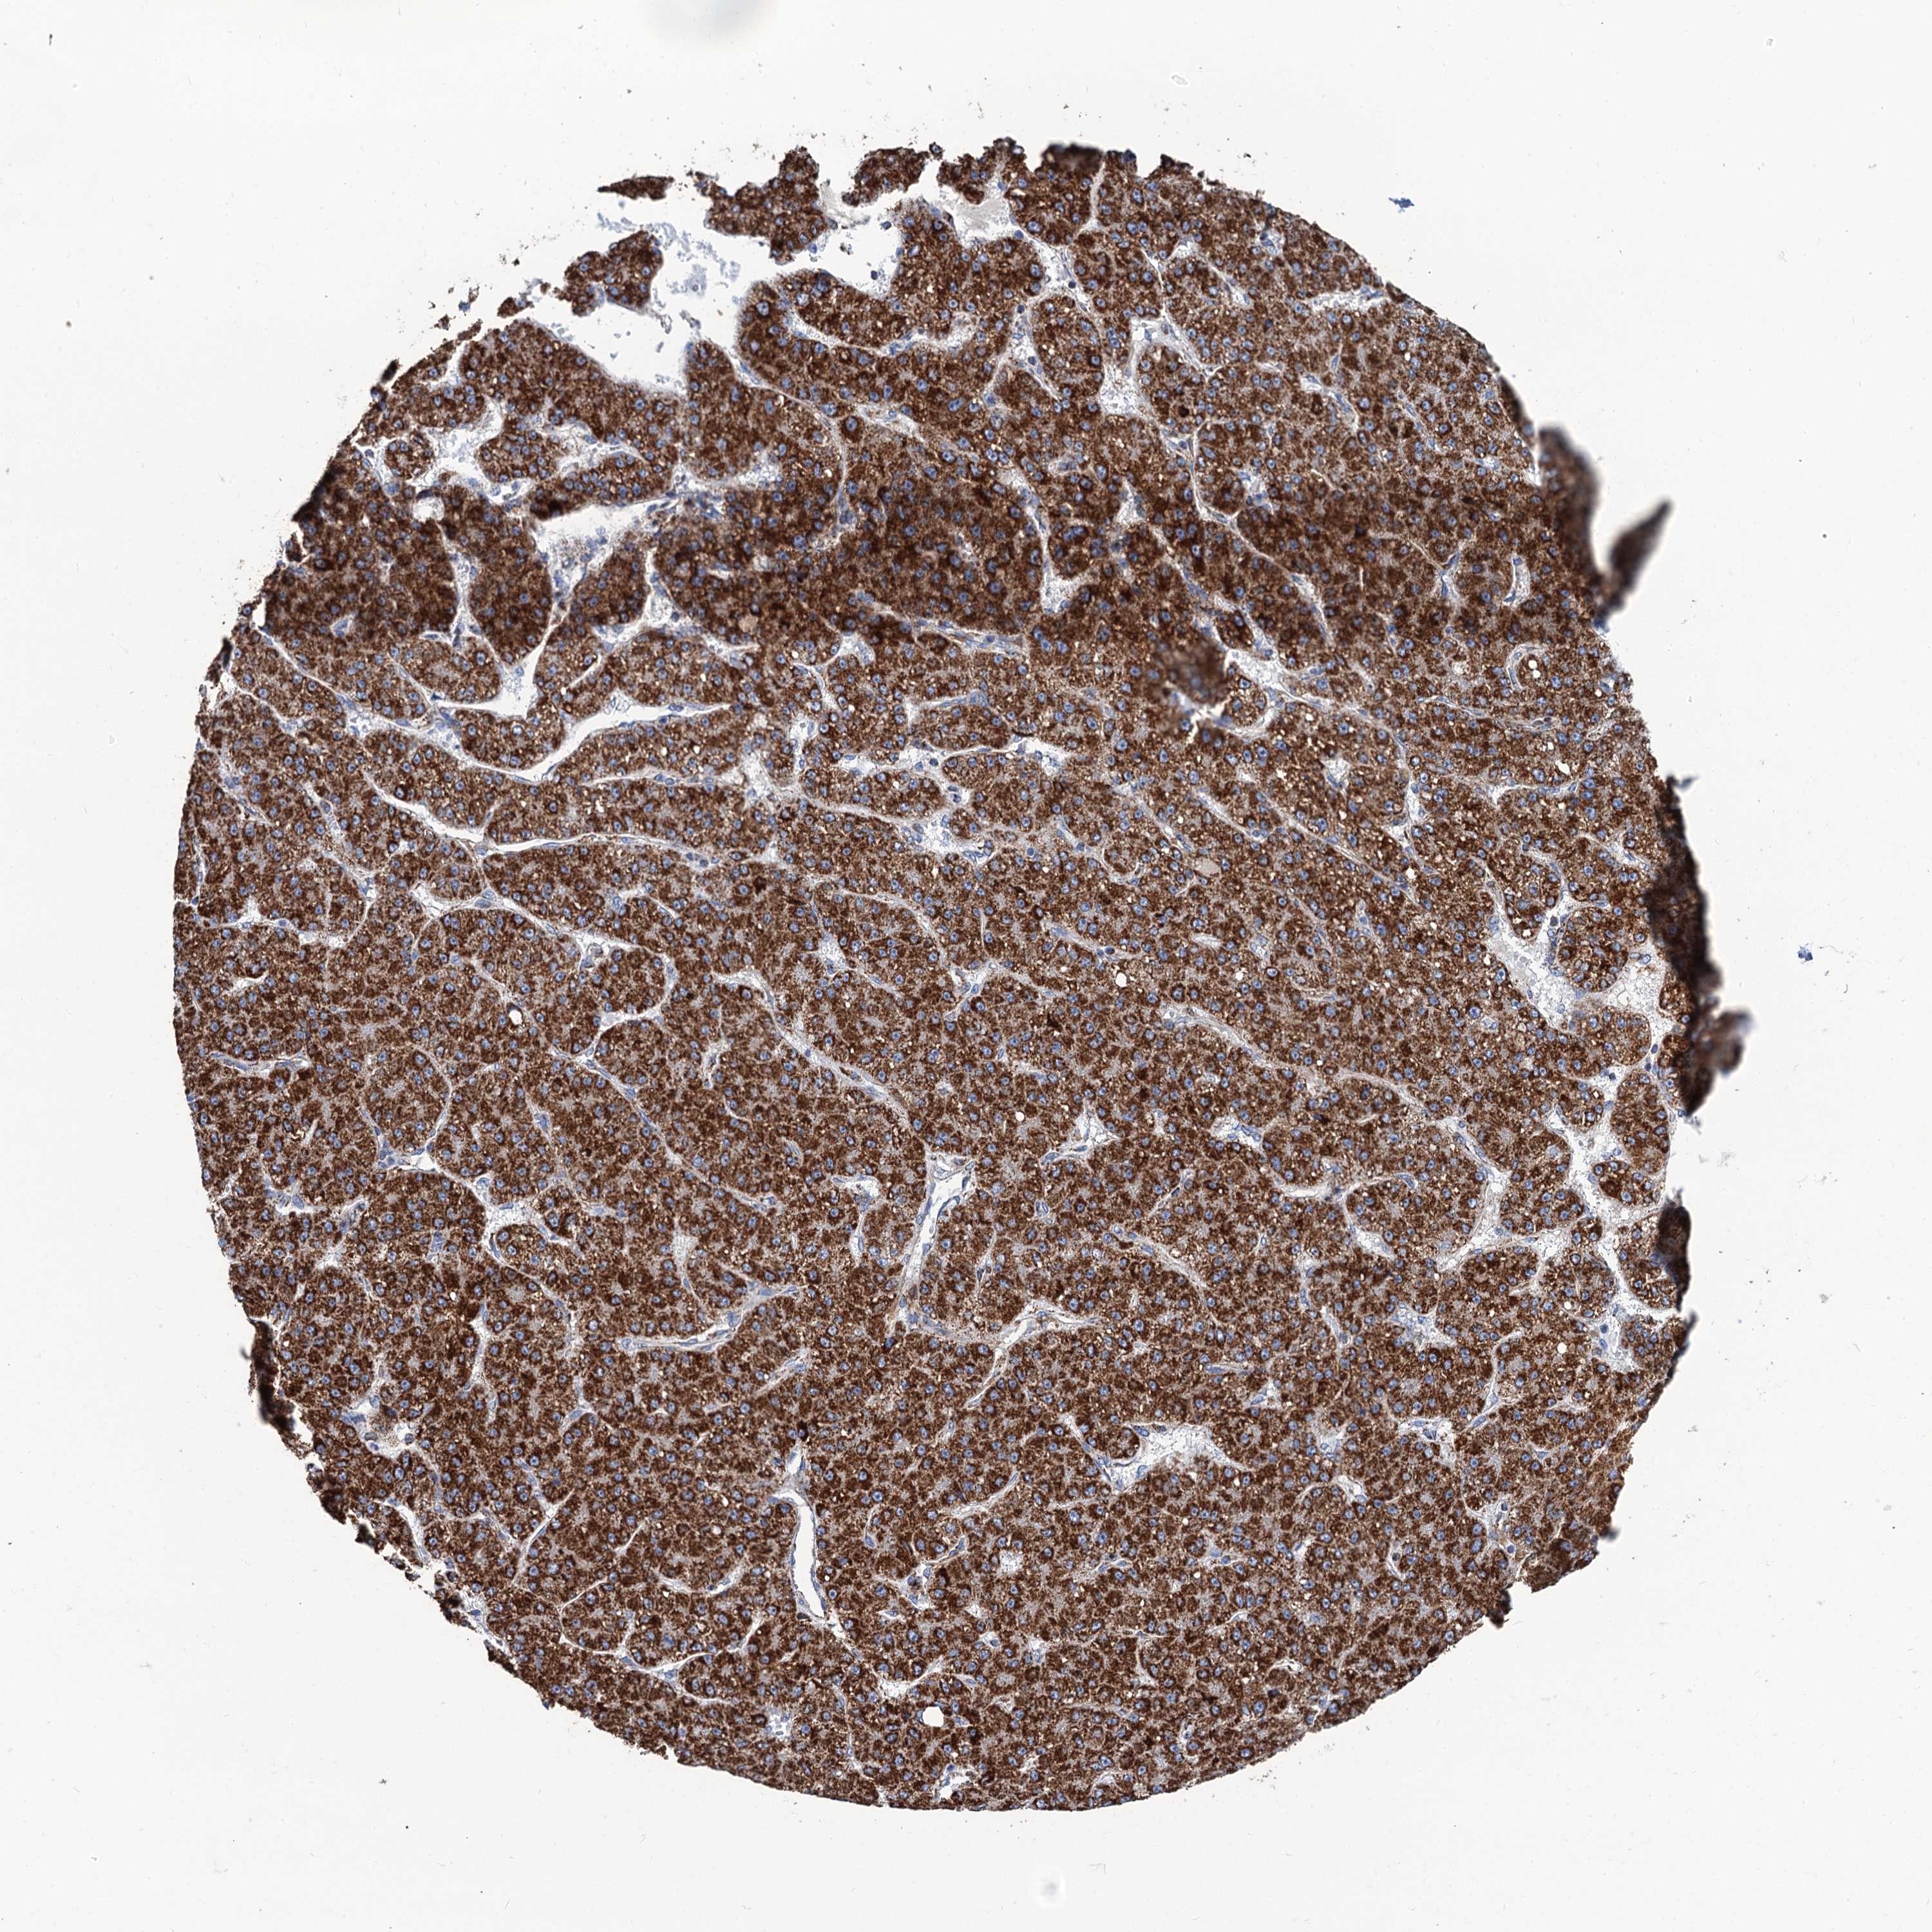

LIVER CANCER - Protein expressioni

A mouse-over function shows sample information and annotation data. Click on an image to view it in a full screen mode. Samples can be filtered based on level of antibody staining by selecting one or several of the following categories: high, medium, low and not detected. The assay and annotation is described here.

Note that samples used for immunohistochemistry by the Human Protein Atlas do not correspond to samples in the TCGA dataset.

Antibody stainingi

Antibody staining in the annotated cell types in the current human tissue is reported as not detected, low, medium, or high, based on conventional immunohistochemistry profiling in selected tissues. This score is based on the combination of the staining intensity and fraction of stained cells.

Each image is clickable and will lead to virtual microscopy that enables deeper exploration of all samples and also displays staining intensity scores, fraction scores and subcellular localization as well as patient and tissue information for each sample.

Antibody HPA041391

Antibody HPA044250

Staining

High

Medium

Low

Not detected

Intensity

Strong

Moderate

Weak

Negative

Quantity

>75%

75%-25%

<25%

None

Location

Nuclear

Cytoplasmic/membranous

Cytoplasmic/membranous,nuclear

Cholangiocarcinoma

Carcinoma, Hepatocellular, NOS